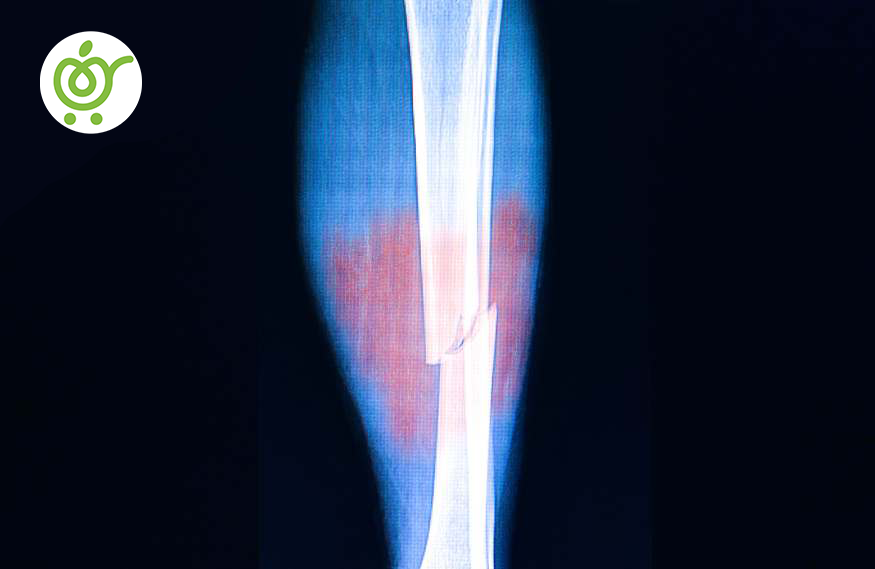

شکستگی استخوان به عنوان یک وضعیت آسیبی توصیف میشود که استخوان تحت تأثیر نیرویی قرار گرفته و به طور جزئی یا کامل شکسته میشود. این مسئله میتواند ناشی از برخورد مستقیم با نیروی ضربهای یا فشاری باشد، که ممکن است از مواقع مختلف مانند حوادث ورزشی یا حوادث خودرو ناشی شود.

شکستگی استخوان ممکن است در هر قسمتی از بدن اتفاق بیافتد، از جمله اندامها، استخوانهای آرنج، پا، مچ، و حتی استخوانهای کمر. علل مختلفی برای شکستگی استخوان وجود دارد که شامل:

نوع ضربه به استخوان میتواند متنوع باشد، از ضربات مستقیم و شدید که منجر به شکستگی میشوند، گرفته تا ضربات مکرر و کمشدت مثل در ورزشهای تماسی. زمین خوردن و حوادث مشابه نیز از عوامل موثر در ایجاد شکستگی استخوان هستند.

آسیب به استخوان میتواند شامل شکستگی کامل یا ناقص، آسیب به بافتهای مجاور از قبیل عروق و عصبها، و یا التهاب استخوان باشد. علائم این آسیبها معمولاً شامل درد حاد، تورم، و ممکن است تغییر در شکل استخوان مصدوم و محدودیت در حرکت باشد. در بعضی موارد، استخوان مصدوم حساسیت نسبت به لمس دارد.